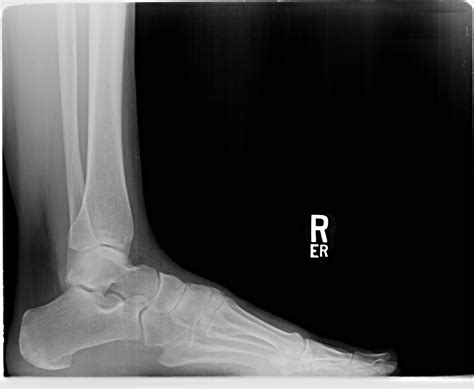

A Lateral Ankle Xray is a specific type of X-ray that provides a side view of the ankle. This view is particularly useful for assessing the alignment of the bones and identifying fractures or dislocations. The lateral view complements other views, such as the anteroposterior (AP) and mortise views, to give a comprehensive picture of the ankle's condition.

Interpreting a Lateral Ankle Xray requires a trained eye to identify key features and abnormalities. Some of the important aspects to look for include:

• Bone alignment: Ensuring that the bones are properly aligned and there are no signs of fractures or dislocations.

• Joint space: Assessing the width and uniformity of the joint space to detect any signs of arthritis or other joint issues.

• Soft tissue swelling: Identifying any swelling or inflammation around the ankle that may indicate an injury.

Radiologists and orthopedic specialists are trained to interpret these images and provide a detailed report of their findings. This report is then used to guide treatment decisions.

Common Findings on Lateral Ankle Xray

Some of the common findings on a Lateral Ankle Xray include:

• Fractures: Visible breaks in the bones, which may be simple or complex.

• Dislocations: Misalignment of the bones, often due to severe trauma.

• Osteoarthritis: Changes in the bone structure and joint space indicative of degenerative joint disease.

• Soft tissue swelling: Inflammation or edema around the ankle, which may be due to injury or infection.